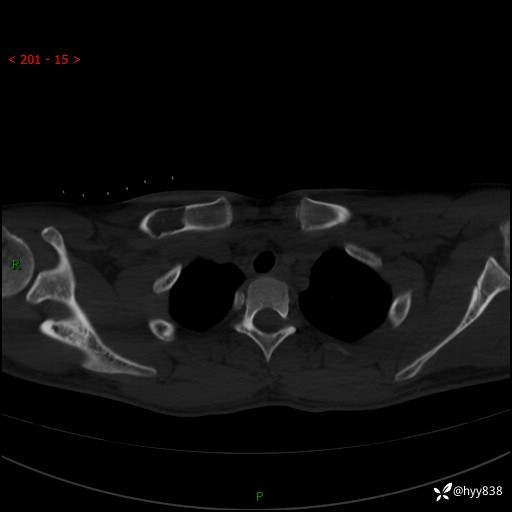

CT